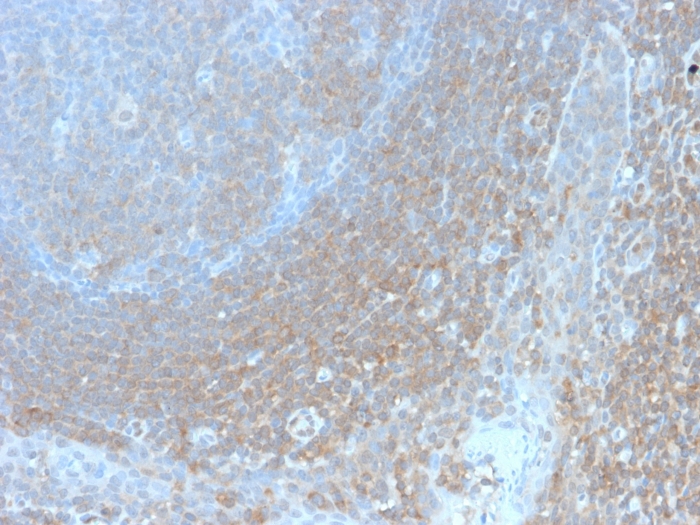

IHC-P analysis of human tonsil tissue section using GTX02597 BCL10 antibody [BL10/2988R].